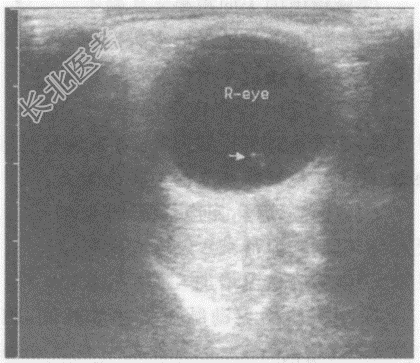

- 单项选择题男,52岁, 自述双眼前有漂浮物(飞蚊症),视力下降半年余。超声综合描述: 玻璃体内可见点状中等回声,不与球壁相连, 随眼球运动而移动。超声提示:

B、玻璃体混浊